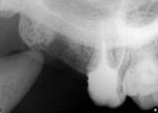

antes depois